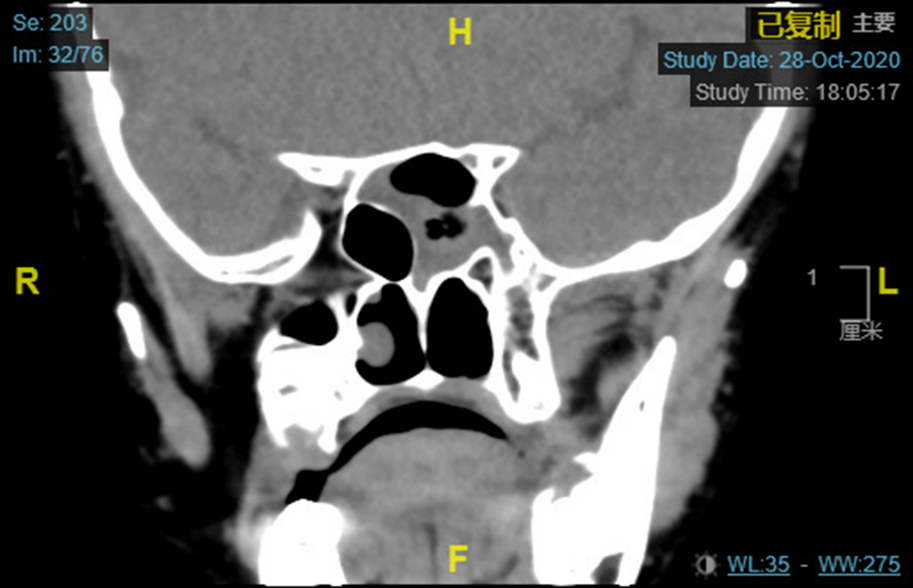

碟筛出血/没有明确的骨折或移位

儿童TON表现为视力下降,RAPD(+),HRCT征象包括后组筛窦或蝶窦腔内积血,视神经管骨折或不明显,视神经显著增粗、扭曲扩张,球后肌锥内,特别是眶尖部血肿或气肿。

左图 成人的视神经管骨折显示骨折碎片右图 儿童的视神经损伤仅表现为骨折线